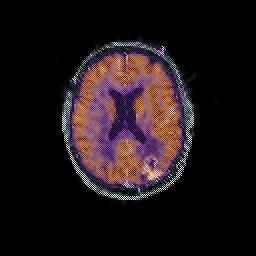

Glioma overlay -- Slice #70

[Home][Help][Clinical] Slice 70